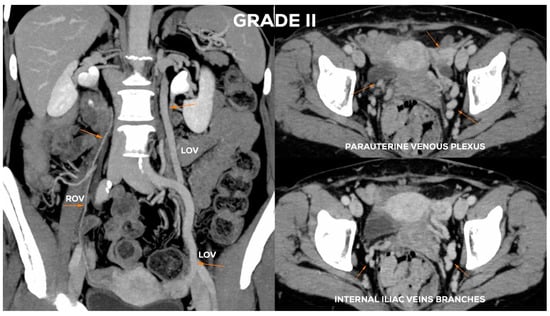

4.2.3. Grade II (GII)

| GII | <7 | (+) | <6.5 | <6 | <5.5 | (−) | <5.5 | <5.5 |